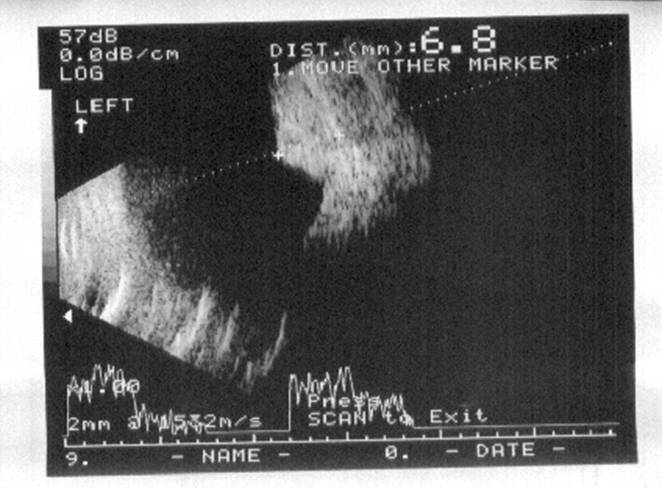

B-scan ultrasound shoed the lesion to be solid, with a height of 6.8mm and had low internal reflectivity.